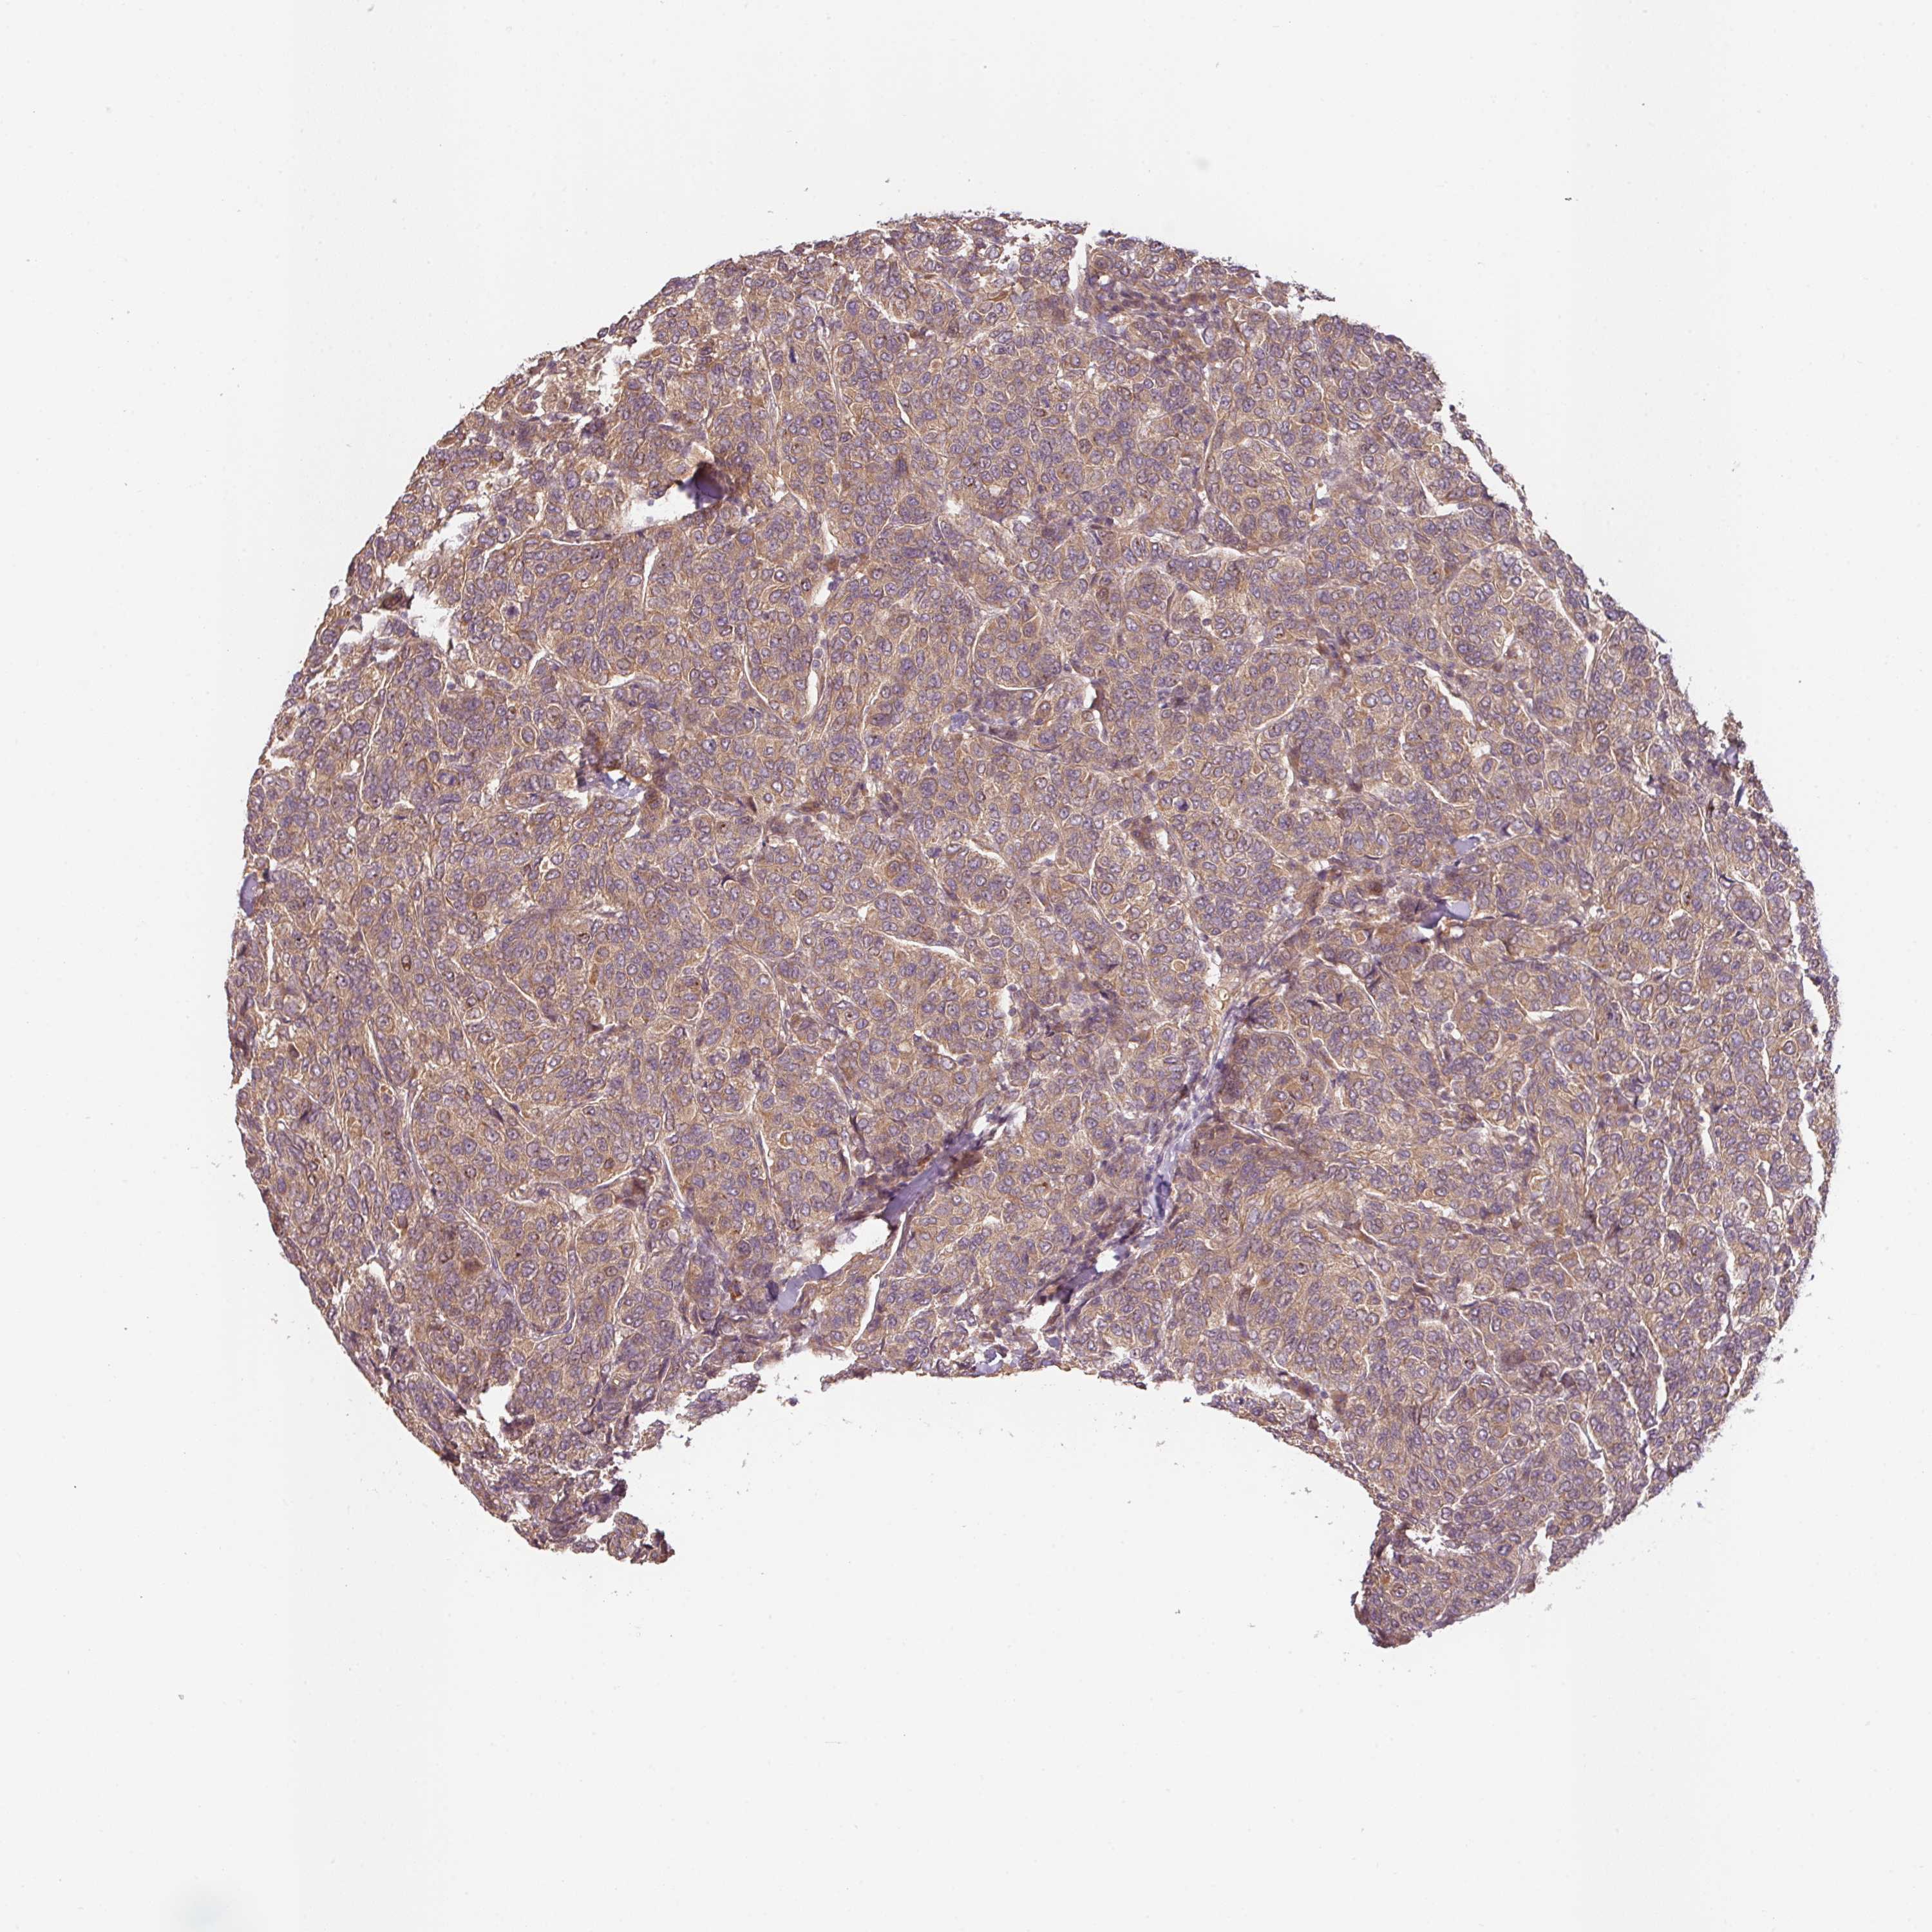

CANCER BREAST CANCER Show tissue menu

BRCA TCGA BRCA VALIDATION PROTEIN EXPRESSION

Breast cancer

Human cancer

Breast invasive carcinoma

RNF31 is not prognostic in Breast Invasive Carcinoma (TCGA)